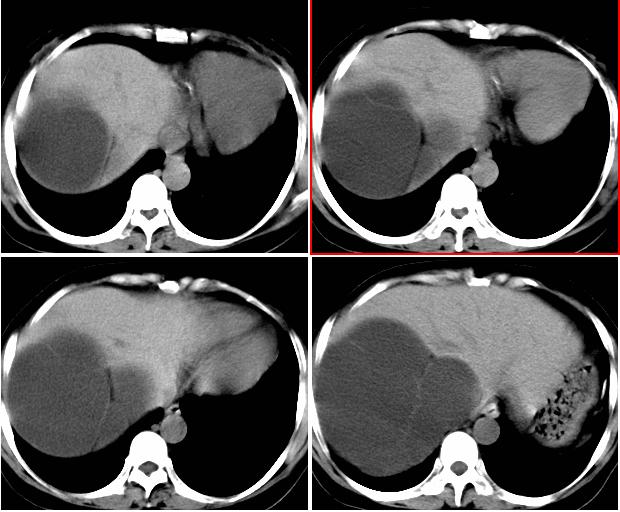

女,52岁,外伤后一小时入院,腹部b超示盆腹腔巨大无回声包块,右肾大小约208*107mm,追问病史,腹部逐渐隆8年余,无明显体重下降、消瘦、黑便呕血史,无大便性状改变,2年前已停月经,有高血压病史8年余,pe:血压180/100mmhg,全身皮肤粘膜无黄染、苍白,全身浅表淋巴结无肿大,腹部膨隆,呈蛙腹,可触及腹部有一14*15cm大小包块,质软,边界清楚,移动度可,无压痛,叩诊呈浊音。辅助检查:肝功能白蛋白43g/l球蛋白35.2g/l余指标正常,血糖电解质凝血四项正常。血常规hb115g/l白细胞13*10/9/l n0.85肾功能bun6.53mmol/l cr124umol/l.

右侧后腹膜巨大囊性肿块影阴,边缘清晰,内见膜状分隔,均匀水样密度,右肾影阴消失,囊块所到区域脏器受挤移位,右侧输尿管扩张,应该考虑:右肾重读积水,巨大肾囊肿不除外。引发肾性高血压。

腹部巨大囊性占位,膨胀性生长,边界光整,囊内容物为水样密度,其内可见多发分隔,纵观所有层面,正常右肾未见,考虑为来源于右肾的巨大多房性肾囊肿(多房性囊性肾瘤)可能性大。

该病来源和病因不明,儿童为先天性,多在5岁以下发病,成人多见于40-70岁女性,ct表现:单房或多房囊性病灶,有厚的囊壁,大部分有分隔,部分可出现环形、沙粒状钙化。

腹部巨大囊性占位,膨胀性生长,边界光整,囊内容物为水样密度,其内可见多发分隔,右恻输尿管全程扩张,纵观所有层面,正常右肾未见,考虑为来源于右肾的巨大多房性肾囊肿可能性大。

反推一下:1.那么重的积水,引起积水的原因大部分是右侧输尿管有梗阻,排出受阻。右侧输尿管应该也是重度扩张才对。2.如果是肾积水,而且是右侧输尿管问题引起,那么病人肯定有相应的临床症状:比如输尿管结石引起的血尿、剧痛等症状,至少也会急性发作病史。另,本例显然不需要考虑输尿管癌,膀胱也挺好,更没有无痛性血尿病史。病人8年多没有其他的不舒服,只是腹部日渐膨隆,临床症状显然不支持。3.如果是重度肾积水的话,应该可以看到被压缩的肾皮质,即使很菲薄也多少会有显示的。

右肾明显扩大,皮质菲薄,间隔细,右输尿管全程扩张,右肾重度积水,原因应重点查输尿管膀胱接合处。